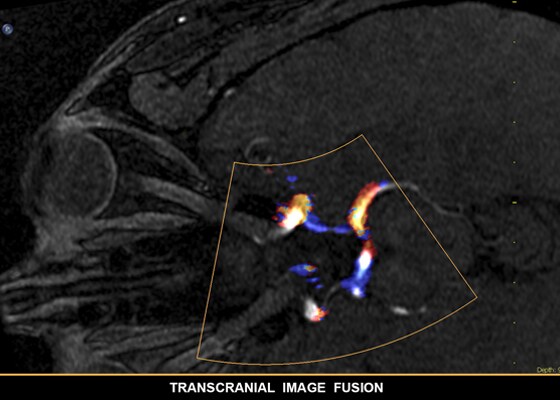

SmartFusion sorgt für einen besseren Einblick und hohe Sicherheit bei Diagnose und Behandlung; EchoNavigator verknüpft Live-3D-TEE und Echtzeit-Radiographie, damit Implantate in 3D dargestellt und dadurch intuitiv in kürzerer Zeit eingebracht werden kann.

Anatomische Intelligenz wendet adaptive Systemintelligenz mit anatomischen 3D-Modellen auf die Ultraschalldaten eines Patienten an, um schnell und einfach reproduzierbare Ergebnisse zu liefern. Mit fortschrittlichen Funktionen für die Organmodellierung, Erstellung von Schnittbildern und Quantifizierung ermöglicht die Anatomische Intelligenz eine einfachere Durchführung und bessere Reproduzierbarkeit von Ultraschalluntersuchungen und liefert gleichzeitig aussagekräftige klinische Ergebnisse, um den wirtschaftlichen und klinischen Herausforderungen der heutigen Gesundheitsumgebung gerecht zu werden.

Anatomische Intelligenz kommt bei Philips Bildgebungslösungen wie EPIQ Affiniti und EchoNavigator zum Einsatz und stattet Klinikteams mit ausgereiften aber dennoch benutzerfreundlichen Verarbeitungstools aus. Dabei ermöglicht sie die zuverlässige Identifizierung von anatomischen Strukturen und Anomalien die Beurteilung des Krankheitsstatus die Ermittlung der passenden Behandlung und die Durchführung geführter Eingriffe in kürzester Zeit.